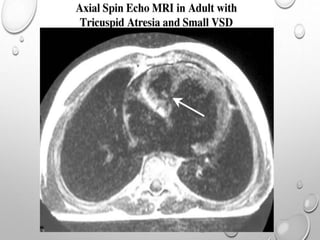

Magnetic resonance imaging (MRI) and computed tomography

(CT) scan

OTHER LABORATORY STUDIES Pulseoximeter and blood gas values are useful in quantitating the degree of hypoxemia, thereby indicating the severity of pulmonary oligemia. Hemoglobin and hematocrit values are useful in children; the degree of polycythemia is useful in estimating the severity of hypoxemia. Magnetic resonance imaging (MRI) and computed tomography (CT) scan